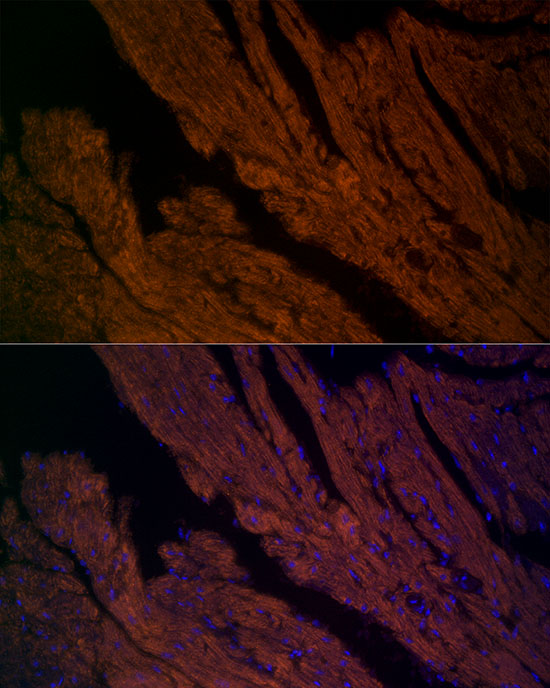

Immunofluorescence analysis of paraffin-embedded mouse heart using RYR2 Rabbit pAb at dilution of 1:200 (40x lens).